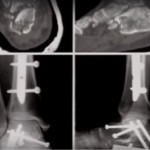

- NECK is non articular. Fracture of talus neck can lead to a vascular necrosis and arthritis of subtalar joint.

- Fracture of the lateral process is usually seen in snow boarders hence also called snowboarder’s ankle.

- Sometimes it may be missed out in X-ray and may be confused as ankle sprain.

- Posterior process composed of 2 tubercles medial and lateral, in between these 2 tubercle there is a groove for FHL. Fracture of posterior process can be sometimes occult.